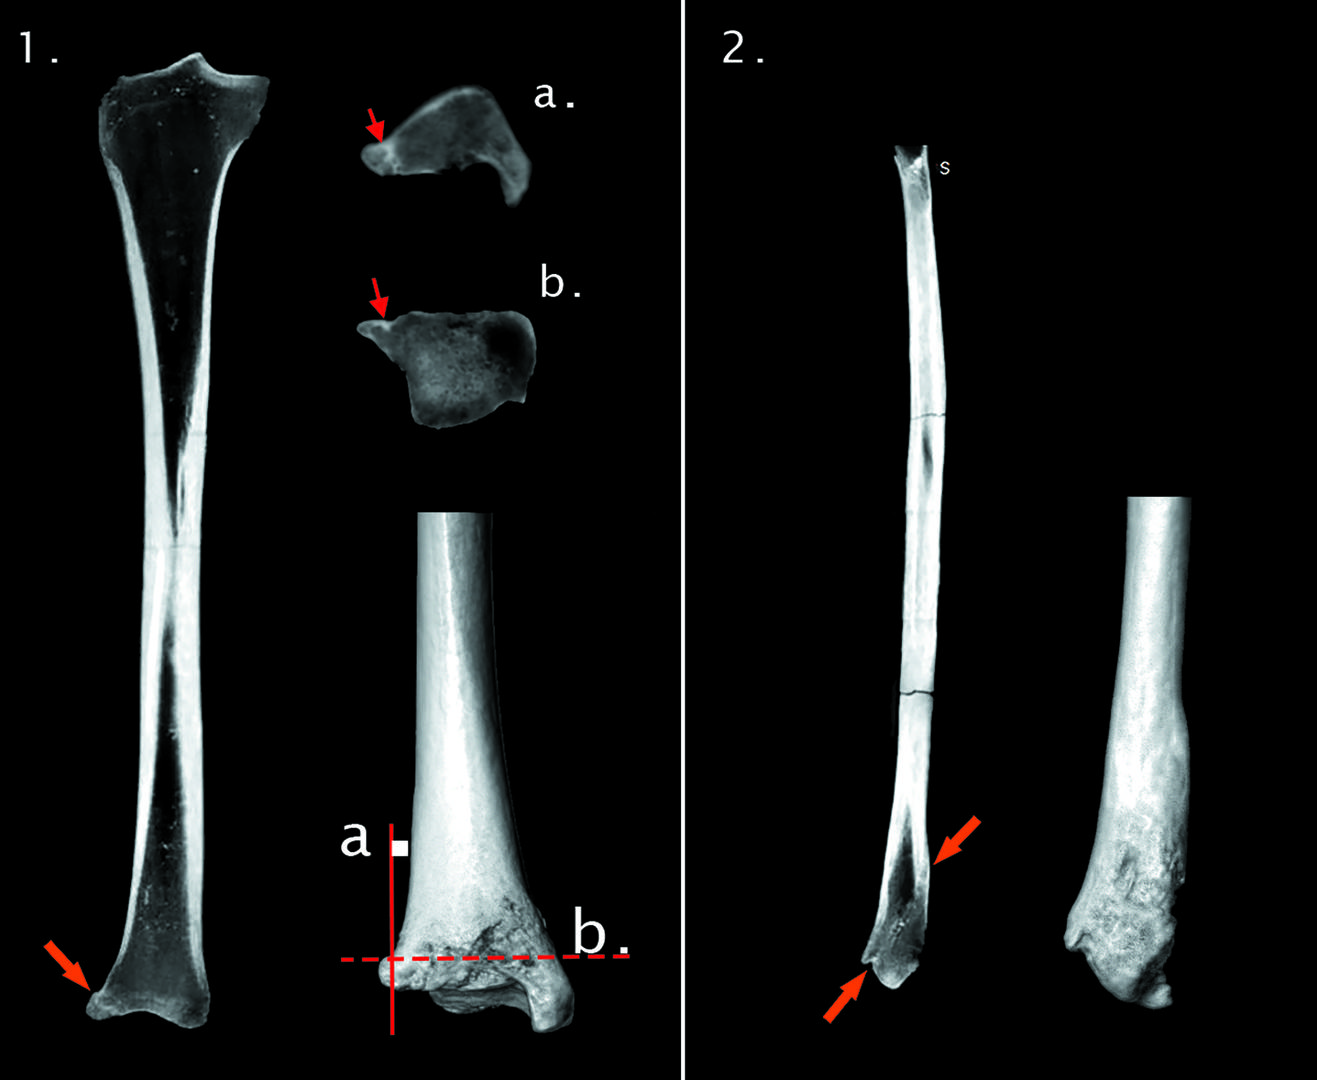

Bioarheološka analiza koštanih ostataka je pokazala da je riječ o ženi staroj između 40 i 50 godina. Riječ je o osobi relativno dobrog zdravlja (za ono razdoblje) koja je patila od nekih sitnijih tegoba kao što su karijesi i degenerativne promjene na kralježnici (artritis), ali to je sve sukladno njenoj dobi.

- Ono što smo također zabilježili jest stara zarasla ozljeda (fraktura) desnog skočnog zgloba što je vjerojatno rezultiralo poremećajem u hodu (šepanjem). Na jednom znanstvenom skupu u Zagrebu sreli smo se s kolegom Fabiom Cavallijem iz Trsta, jednim od vodećih europskih paleoradiologa i stručnjaka za rekonstrukciju lica, koji se ponudio da će napraviti rekonstrukciju lica ove osobe na temelju kostiju lubanje. Kostur smo odvezli u Trst gdje je u Općoj bolnici čitav kostur snimljen na CT-u i na temelju tih snimki je kolega Cavalli napravio idealnu rekonstrukciju lica tako da možemo slobodno reći da smo ju ponovno „vratili u život“ nakon ponovo 500 godina, kaže naš sugovornik.